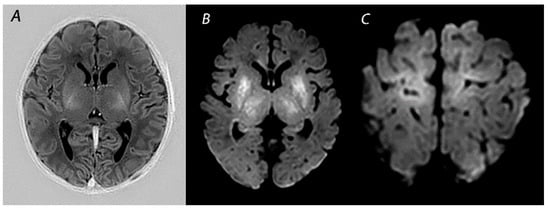

6. HIE Mimics